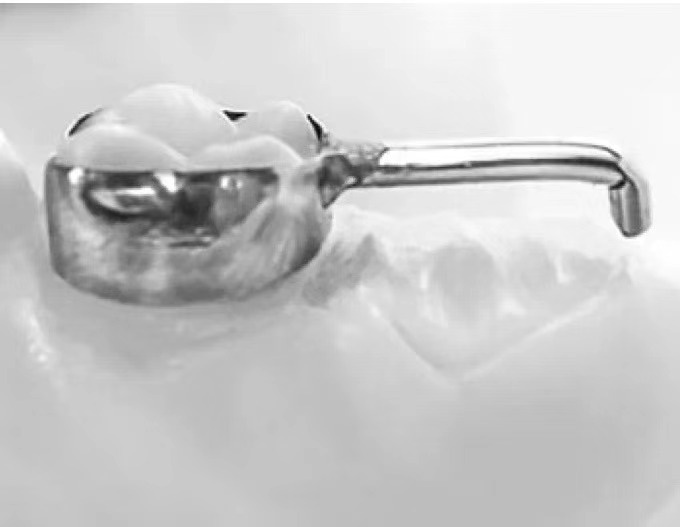

乳牙作为儿童的咀嚼器官,具有咀嚼、发音、美观及维持牙弓长度,促进颌面部正常发育的作用;同时乳牙作为天然的间隙保持器,可以很好地诱导恒牙的正常萌出。而临床由于严重的龋病、牙髓根尖周疾病及外伤等原因会导致乳牙过早丧失。乳牙过早缺失,将可能影响继承恒牙的正常萌出而造成恒牙排列不齐。乳前牙早失还会导致发音障碍,并且影响美观,甚至引起儿童心理问题。乳尖牙或乳磨牙早失后,发生恒牙列错畸形的机会比无乳牙早失者高3~4倍。 儿童牙齿早失后,为防止邻牙向缺隙部位倾斜和对颌牙伸长,可设计间隙保持器保持早失牙齿的近远中间隙和垂直间隙,促进继承恒牙正常萌出。 间隙保持器的种类 间隙保持器是通过维持早失牙间隙以保障牙弓长度的一种口腔装置,能在不影响患儿正常生长发育的同时,为正常咬合关系的建立提供有利条件。间隙保持器应在拔牙后几周内戴入,间隙丧失通常发生在乳磨牙过早脱落的6个月内。 带环或全冠丝圈式间隙保持器 主要适用于单侧单颗乳磨牙早失的治疗。 舌弓式间隙保持器 Nance弓(腭弓)式间隙保持器,主要适用于单侧或双侧多颗乳牙早失的治疗。 可摘式间隙保持器 主要适用于单颗或多颗乳牙早失的治疗,在保持间隙的同时,还能恢复部分咀嚼功能。 远中导板式间隙保持器 适用于第二乳磨牙早失、第一恒磨牙尚未萌出或萌出中。 间隙保持器注意事项 1. 保持器粘结后2小时内不能进食,待粘结材料完全固定后方可正常使用; 2. 保持良好的口腔卫生习惯,用牙刷和牙线清除牙菌斑和食物残渣; 3. 避免咀嚼硬而黏的食物; 4. 避免用舌头抵制保持器; 5. 前期1~3个月复诊,后期3~6个月复诊,直至恒牙萌出; 6. 若保持器松动移位或破裂,及时复诊。 佩戴间隙保持器后常见问题及解答 Q 间隙保持器佩戴后会不舒服吗? A 刚戴上间隙保持器会有几天的不适感,唾液增多和吐字不清也是正常的,佩戴后小朋友能很快适应。 Q 间隙保持器要佩戴多久? A 建议长期佩戴,直到替换恒牙长出来,具体时间根据个人实际口腔情况决定。 Q 间隙保持器会引起蛀牙吗? A 正确使用和维护间隙保持器,每天至少刷两次牙,配合使用牙线等清洁工具,并定期进行口腔检查。 Q 间隙保持器需要更换吗? A 在佩戴间隙保持器期间,牙齿可能会出现一些微小的移动,定期复查对于后期的佩戴效果十分关键,建议定期复查,如果出现佩戴不适、脱落等情况,建议及时检查,必要时重新制作间隙保持器。 Q 间隙保持器何时可以摘掉? A 家长可通过观察间隙保持器中间是否有白色牙尖萌出进行判断。